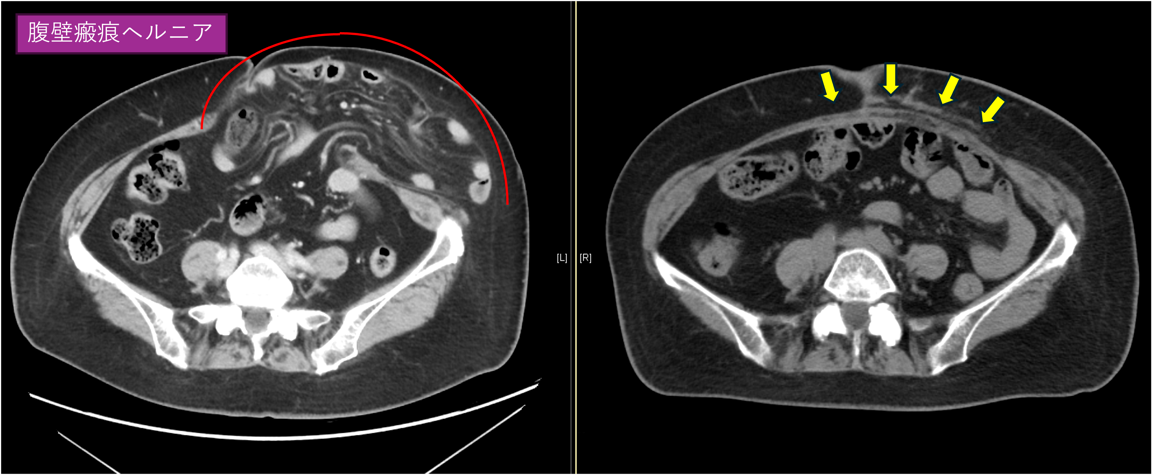

代表的な一例の術前・術後CTを示しますが、きれいに脱出腸管が収納されヘルニアが修復されています(図2)。

図2(CTスキャン):腹壁瘢痕ヘルニア(赤線)、修復後(黄色矢印)